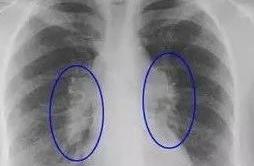

Gouty essence is acid of the make water inside body the level is elevatory, precipitation of acerbity salt of separate out make water is in joint or nephritic place. When coming on, the patient can concern section strut, aching feeling, it is as the tiger like worry joint.

Traditional Chinese medical science of short for Zhejiang Province is big doctor of Li Xiao roc ever had examined divisions of 2 courtyard rheumatism immunity a such young gouty patients. Still going up the small profit of 16 years old of schoolboys of junior high school, appear suddenly in a day of midnight left foot thumb is red heat is painful, hurry to a hospital, the examination comes down to discover uric acerbity prep above L of / of 600 μ Mol, double can CT shows there are crystallizations of a lot of uric acerbity salt in left foot thumb, be by diagnose gouty. It is medium commonly senile male is sent more, how can teen-age boy get this trouble? In hospitalization, doctor of Li Xiao roc enquired the circumstance such as habit of his medical history, food and life work and rest carefully, the gout that discovers him drinks fruit juice for a long time probably to matter with him.